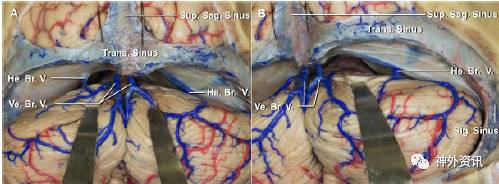

图6. 相对于后正中入路(A),旁正中小脑上入路(B)可以避开几乎所有的小脑蚓部桥静脉。

图7. 后正中入路(A)的显露取决于对山顶的牵拉,而旁正中入路(B)经过的是较低位的外侧小脑。第IV脑神经位于手术区域的下缘。